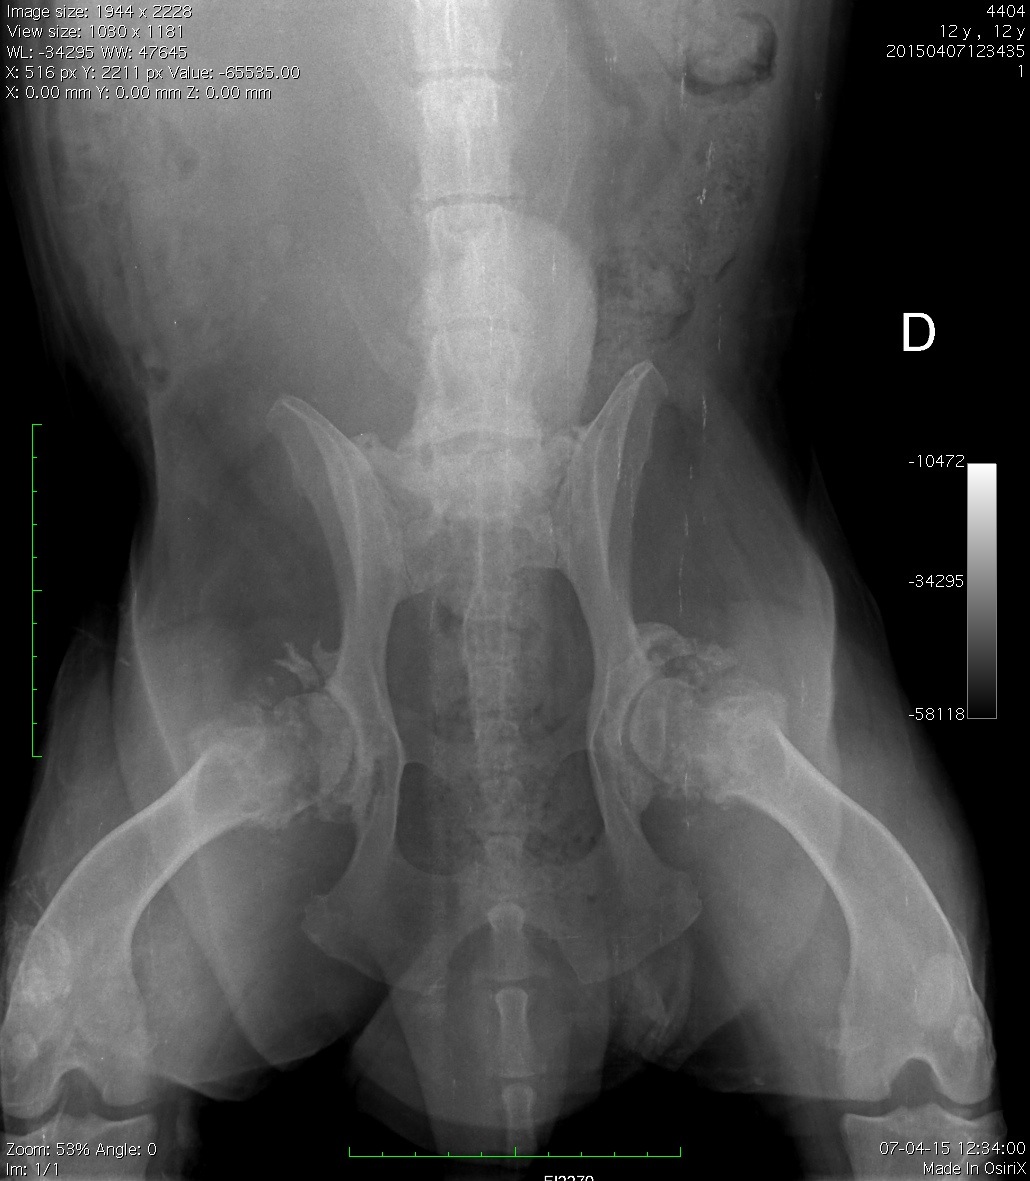

Paciente canino, 12 años, dolor agudo coxofemoral combinado con agresividad a la manipulación

Se adjuntan proyecciones L-L y V-D de columna lumbosacra, pelvis y abdomen caudal.

Respecto a los radiodiagnósticos, podemos afinar que el paciente cursa con:

I. Displasia de cadera

II. Inestabilidad lumbosacra

III. Proceso agresivo coxofemoral

IV. Vértebra transicional